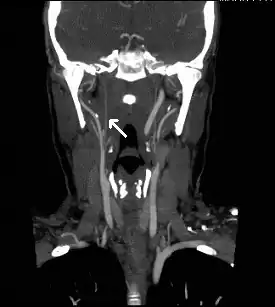

Herpes zoster ophthalmicus (HZO), also known as ophthalmic zoster, is shingles involving the eye.[1] Symptoms generally include a rash of the forehead with swelling of the eyelid.[1] There may also be eye pain, eye redness, and light sensitivity.[1] Before the rash appears tingling may occur in the forehead along with a fever.[1][3] Complications may include vision loss, increased pressure within the eye, and chronic pain.[2][1]

The underlying mechanism involves a reactivation of the varicella zoster virus within the ophthalmic nerve (the first division of the trigeminal nerve).[2] Risk factors include poor immune function, psychological stress, and older age.[2] Diagnosis is generally based on symptoms.[1]